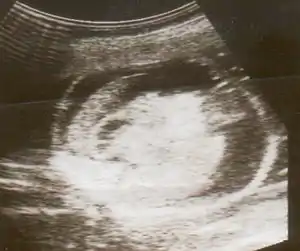

| An ultrasound showing a fetus with hydrops fetalis | |

Hydrops fetalis can be diagnosed and monitored by ultrasound scans.[1] An official diagnosis is made by identifying excess serous fluid in at least one space (ascites, pleural effusion, of pericardial effusion) accompanied by skin edema (greater than 5 mm thick). A diagnosis can also be made by identifying excess serous fluid in two potential spaces without accompanying edema. Prenatal ultrasound scanning enables early recognition of hydrops fetalis and has been enhanced with the introduction of MCA Doppler.[6]